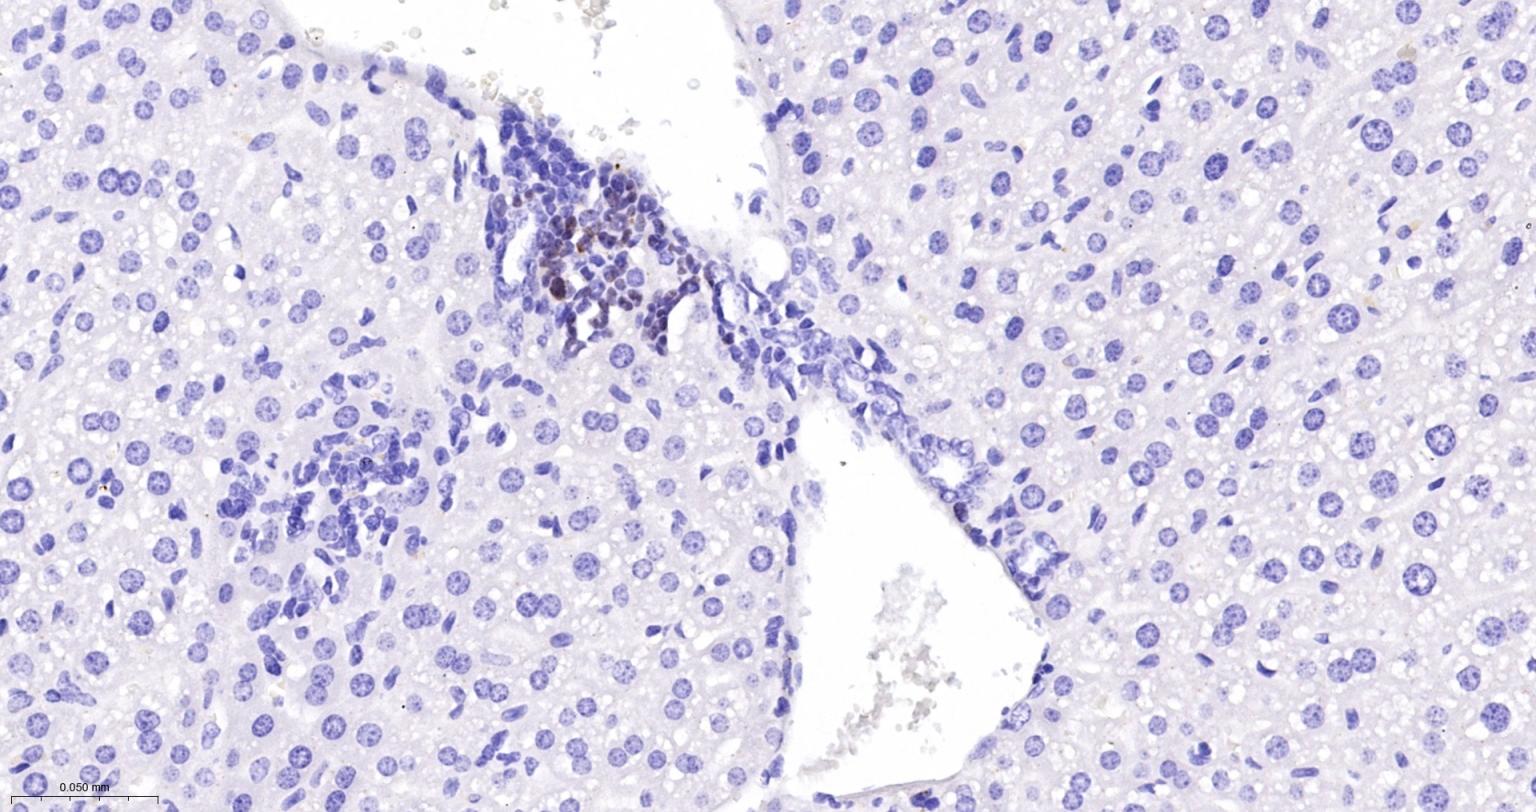

Paraformaldehyde-fixed, paraffin embedded Rat Spleen; Antigen retrieval by boiling in sodium citrate buffer (pH6.0) for 15 min; Antibody incubation with Ki67Monoclonal Antibody, Unconjugated(bsm-52455R) at 1:200 overnight at 4°C, followed by conjugation to the SP Kit (Rabbit, SP-0023) and DAB (C-0010) staining.